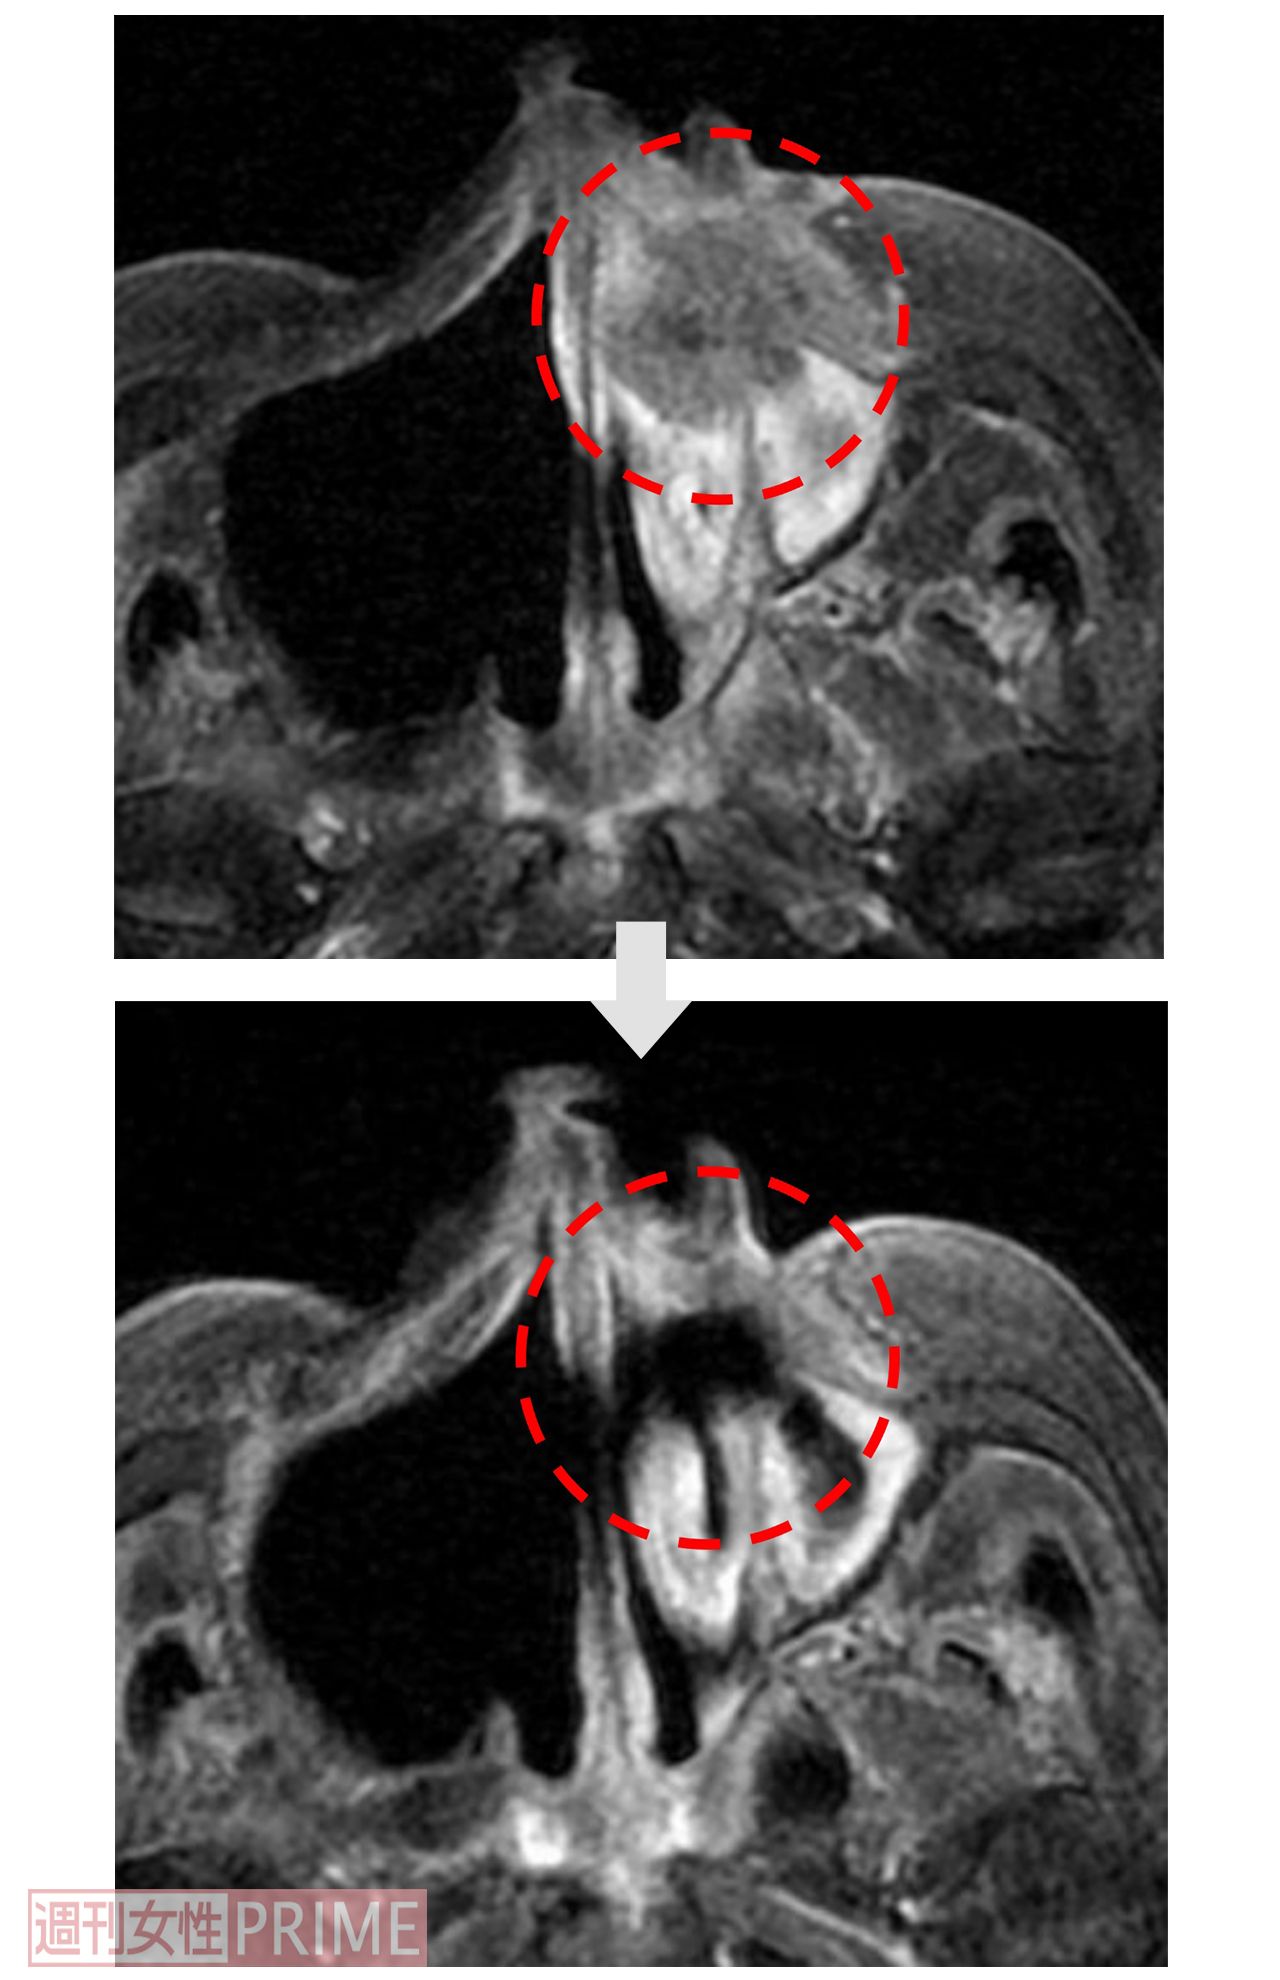

【症例1:70代男性 左上顎洞がん】BNCT治療前後のCT画像

[写真 7/10枚目] 【症例1:70代男性 左上顎洞がん】BNCT治療前後のCT画像